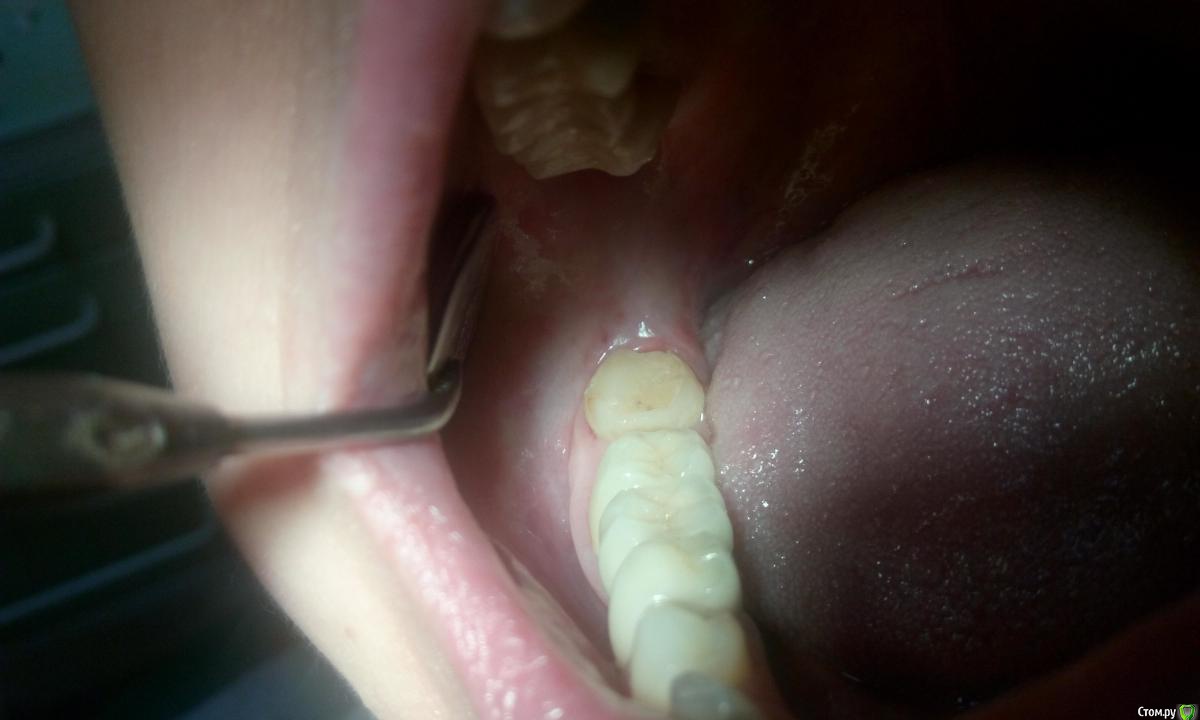

Витторио Орлионе Опубликовано 27 июля, 2016 Поделиться Опубликовано 27 июля, 2016 Обратилась пациентка с жалобами на боль в области зуба 4.8. При осмотре было обнаружено, что дистальная стенка зуба скололась под десну на глубину 4мм и вызвала воспаление десны, что пациентку и привело в клинику. Рядом протянулся мостовидный протез 4.7-4.5 и именно между зубами 4.8 и 4.7 полностью отсутствует контакт и постоянно застревает пища. А после того как сделали снимок было ещё и обнаружено нарушение прилегания коронки зуба 4.7 к его корню.Как мне кажется самым оптимальным было бы удаление зуба 4.8, но вопрос в том а вдруг он понадобиться как опорный для изготовления мостовидного протеза 4.8-4.5??Какова ваша тактика лечения в этом случае уважаемые коллеги: удалить 4.8 и оставить мостик как есть или же если это возможно изготовить новый мостик? Ссылка на комментарий

Finch Опубликовано 28 июля, 2016 Поделиться Опубликовано 28 июля, 2016 Неприкрепленная слизистая окружает от 30 до 60% дистальной поверхности третьего моляра, так что даже при хорошем краевом прилегании вероятность развития парадонтита высока. Да и протез такой протяженности (в случае удаления 7) достаточно опасная конструкция. Мне кажется оптимальным соединить 7 и 8 сейчас. Если не соединить то пища будет забиваться там постоянно даже если сделать максимально плотно. Ссылка на комментарий